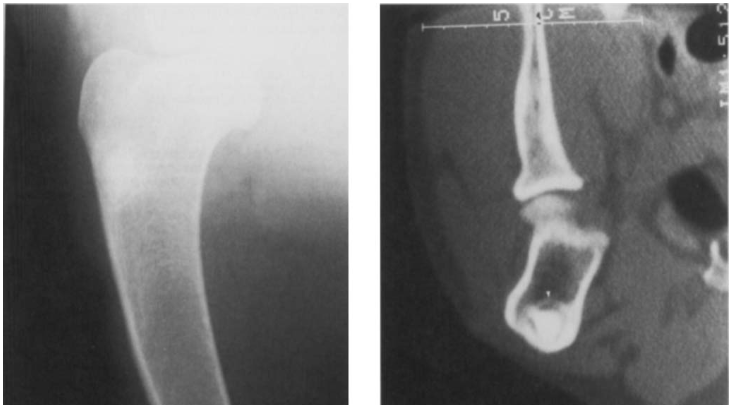

What is the likely diagnosis? Other differentials?

Osteoma is the likely diagnosis

Osteosarcoma

Granuloma

Infarct